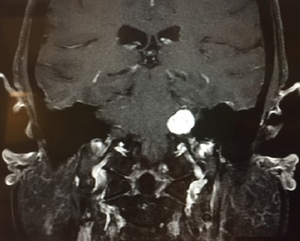

Vestibular schwannoma, also called acoustic neuroma, is the most common tumor of the cerebellopontine angle (located between the cerebellum and pons) and often presents with unilateral or asymmetric sensorineural hearing loss (Figure 1).5 Other symptoms may present in association, including imbalance and tinnitus,5 however, these symptoms are often absent in up to 45% patients diagnosed with acoustic neuroma.2